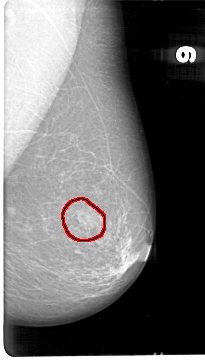

D_4042_1.LEFT_MLO

LEFT_MLO LINES 5386 PIXELS_PER_LINE 3061 BITS_PER_PIXEL 12 RESOLUTION 43.5 OVERLAY

FILE: D_4042_1.LEFT_MLO.OVERLAY

TOTAL_ABNORMALITIES 1

ABNORMALITY 1

LESION_TYPE MASS SHAPE OVAL MARGINS OBSCURED

ASSESSMENT 0

SUBTLETY 5

PATHOLOGY BENIGN

TOTAL_OUTLINES 1

BOUNDARY